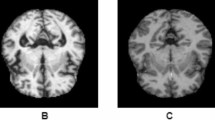

The Alzheimer’s Disease Neuroimaging Initiative (ADNI)18 offers datasets pertaining to Alzheimer’s disease in either Nifti or DICOM formats, representing three-dimensional volumetric data. Engaging directly with three-dimensional datasets presents certain complexities; therefore, the dataset in question was specifically developed to facilitate the application of image processing algorithms with greater ease. This dataset is comprised of two-dimensional axial images derived from the baseline dataset of ADNI, which originally included Nifti images. It encompasses three distinct categories, namely Alzheimer’s Disease (AD), Mild Cognitive Impairment (CI), and Cognitively Normal (CN) individuals. The images were extracted from the ADNI Baseline dataset (NIFTI format), which consisted of a total of 199 instances. The original images are accessible for download at https://ida.loni.usc.edu/login.jsp?project=ADNI.

Preprocessing

Preprocessing was done on each dataset image as follows:

Resizing images to expedite the execution of applications and use less processing power.

Data augmentation, which makes it possible to get fresh training image data sets that are related to the source image. Rotation, flipping both horizontally and vertically, and adjusting width and height are a few techniques that can be applied to improve image recognition and accuracy. In this inquiry, we used zoom, brightness, and horizontal flip approaches as part of our data augmentation strategies in the experiments. Increasing the number of photos as much as possible is the aim here.

Oversampling, which addresses the issue of unbalanced classes by utilizing the SMOTE approach19.

We divided the ADNI dataset images into 80% for train and 20% for test.